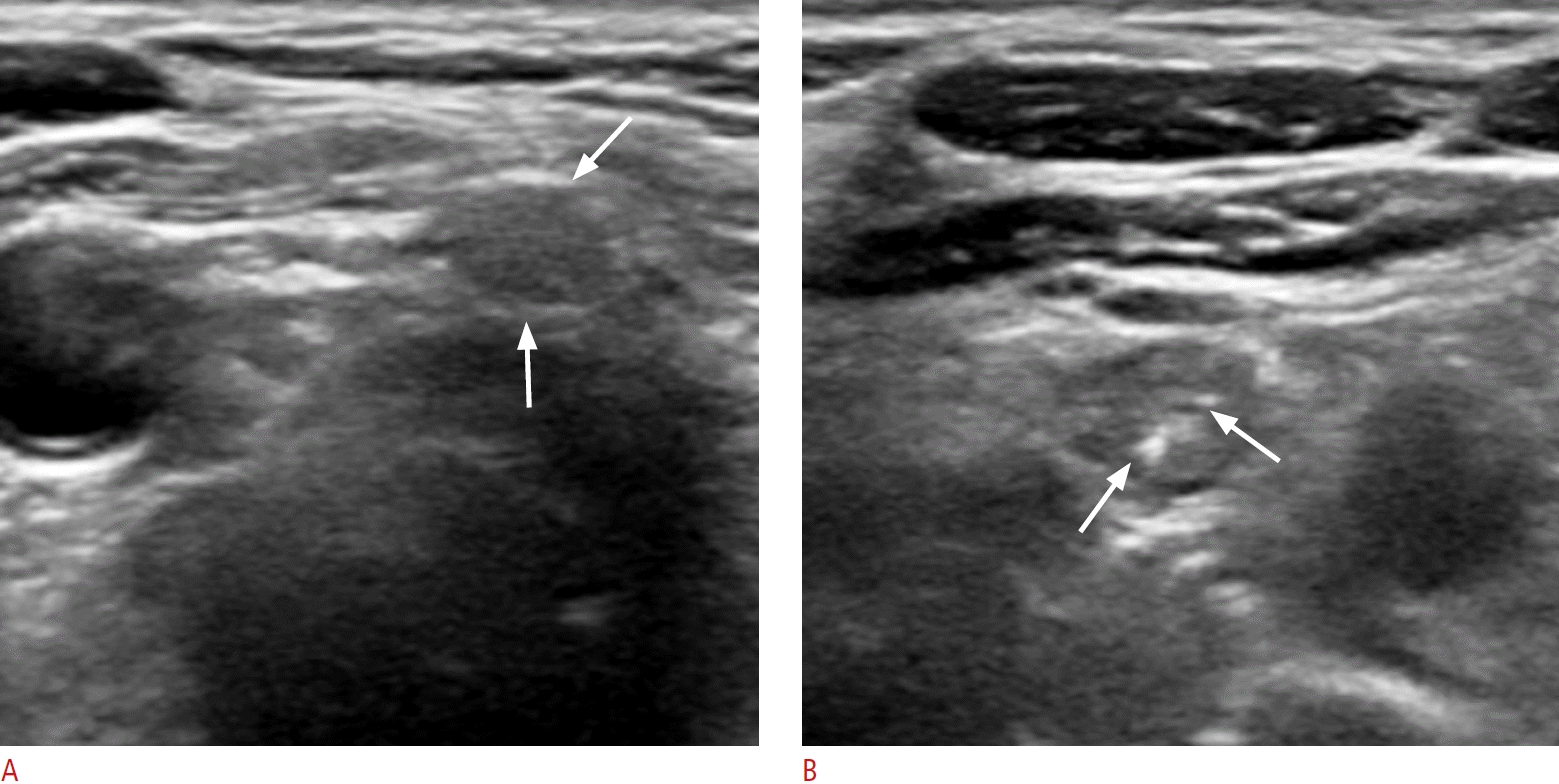

Fig. 3.

Normal parathyroid gland with typical ultrasound features in the infrathyroid paramedian central neck in a 41-year-old female patient (case 5).

A, B. Transverse and longitudinal images show an ovoid, homogeneous, markedly hyperechoic parathyroid gland in the left infrathyroid central neck (arrows).